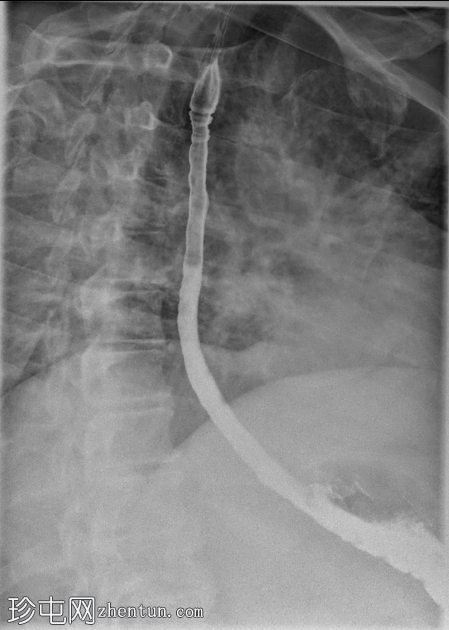

4.png

矢状位

透视食管造影显示食管内可见同心环状轻度狭窄,符合嗜酸性食管炎的影像学表现。近端食管轻度扩张,提示存在固定性狭窄。未见肿块或食管裂孔疝。

钡餐食管造影通常显示固定的同心环(“气管化”)、节段性狭窄或食管管径变细。